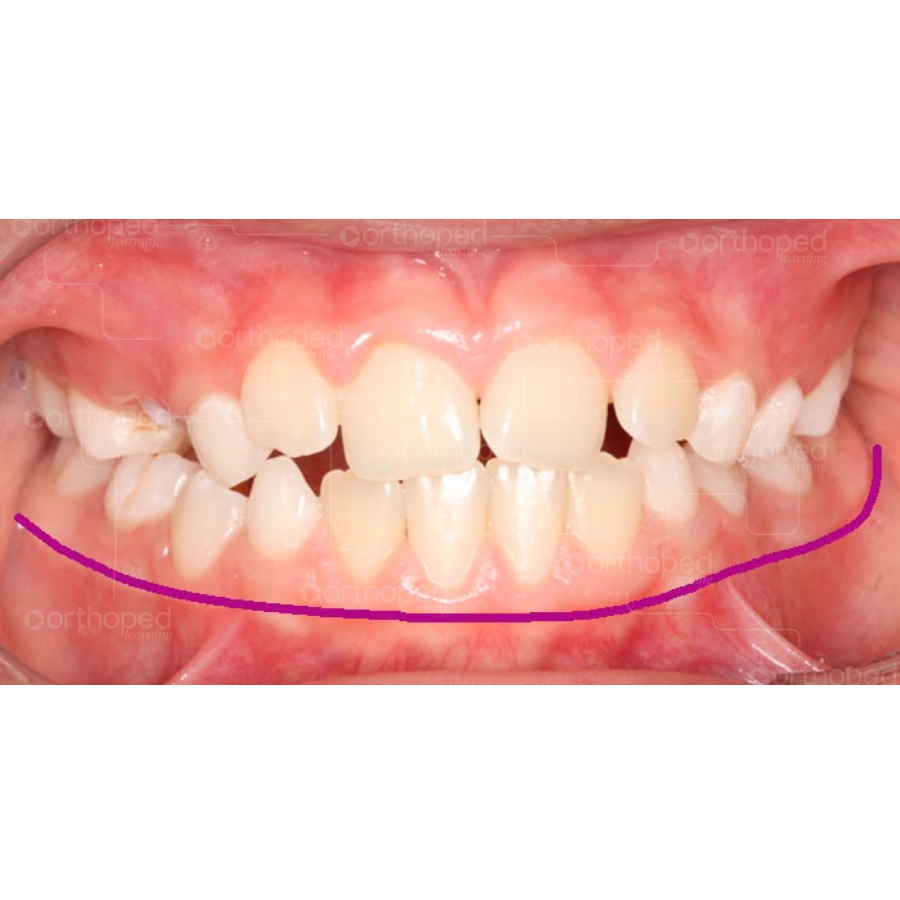

É comum encontrar apinhamento anterior superior, falta de espaço para irrupção dos incisivos laterais superiores, palato profundo, corredor bucal amplo, além de maloclusão de Classe II ou Classe III. Porém, o diagnóstico da atresia maxilar não pode ser baseado em um único critério clínico e sim no conjunto de fatores para definirmos o melhor plano de tratamento para o nosso paciente.